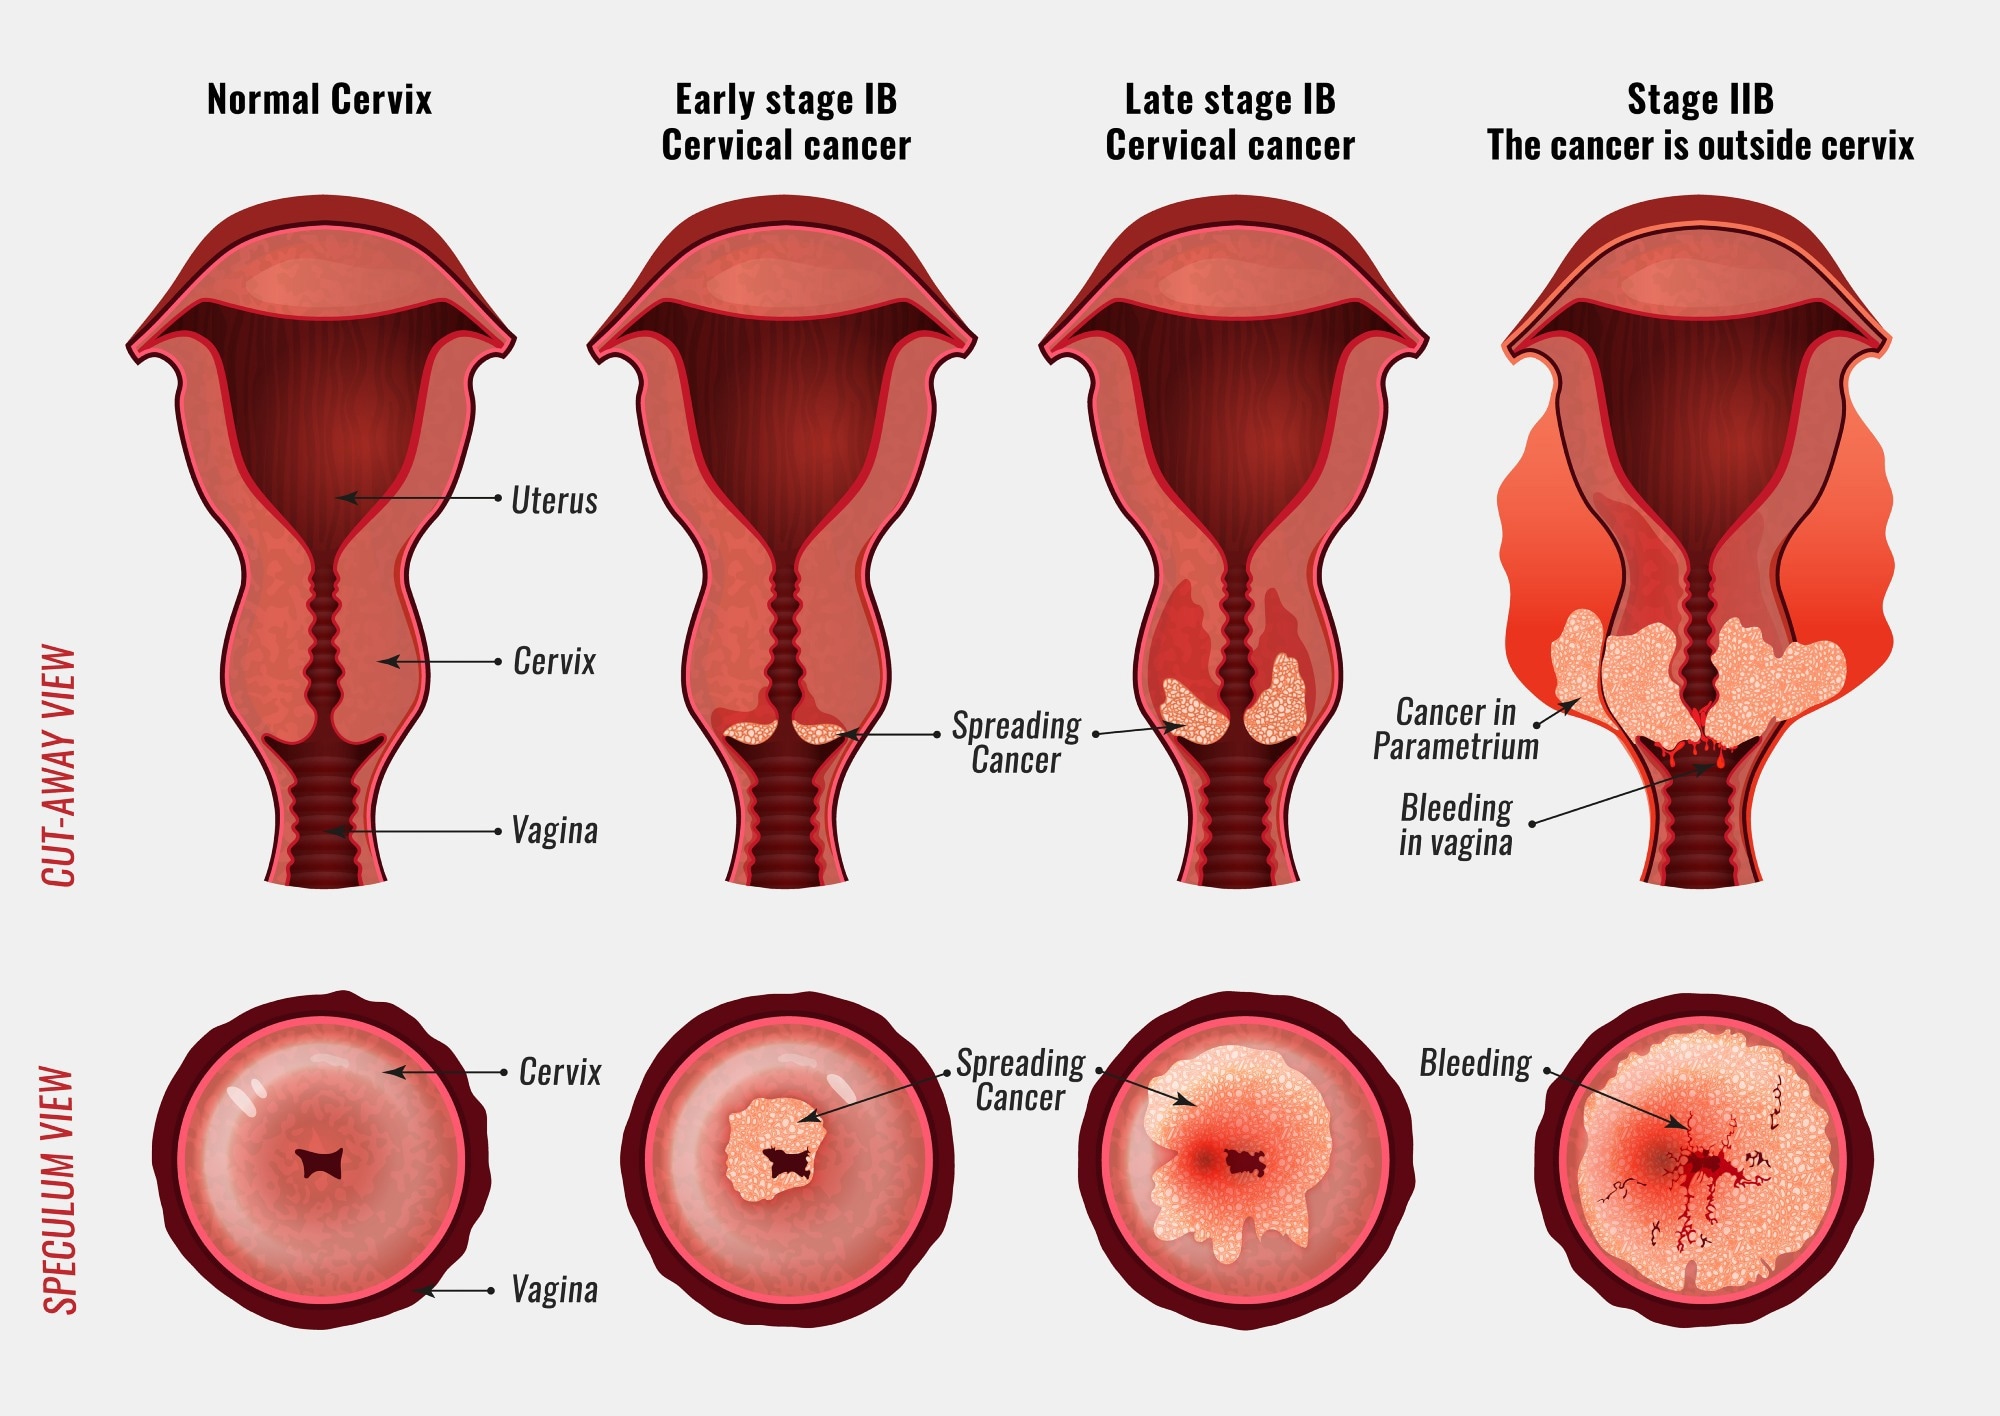

Cervical cancer originates in the cells of the cervix, which is the lower, narrow portion of the uterus that connects to the vagina. Most cervical cancers begin in the transformation zone — the area where the cervix transitions between two types of cells: squamous cells (flat cells lining the ectocervix) and glandular cells (column-shaped cells lining the endocervix).

The two main types of cervical cancer are squamous cell carcinoma, accounting for about 70–90% of all cases, and adenocarcinoma, which develops from the glandular cells. In rare cases, both types may be present simultaneously. Cervical cancer is usually slow-growing, taking years to develop from precancerous lesions into full-blown cancer — which is exactly why early screening is so powerful.

Symptoms: What Women Should Watch For

Early-stage cervical cancer often causes no symptoms, which is one of the reasons regular screening is so critical. As the disease progresses, women may notice:

- Unusual vaginal discharge, which may be watery, bloody, or have an unpleasant odor

- Vaginal bleeding between menstrual periods, after intercourse, or after menopause

- Pelvic pain or pain during intercourse

- In advanced stages: back pain, leg swelling, difficulty urinating, or loss of bladder/bowel control

Diagnosis and Treatment

When a Pap smear or HPV test returns an abnormal result, the next step is usually a colposcopy — a procedure in which the doctor examines the cervix under magnification and may take a small tissue sample (biopsy) for laboratory analysis. If precancerous changes are confirmed, treatment options such as LEEP (loop electrosurgical excision procedure), cryotherapy, or cone biopsy can remove the abnormal tissue before it becomes invasive cancer.

For diagnosed cervical cancer, treatment depends on the stage and may include surgery, radiation therapy, chemotherapy, or a combination. Early-stage cervical cancer (Stage I and II) has survival rates above 80–90% with appropriate treatment. Advanced-stage cancer is significantly harder to treat, which is why early detection is so critically important.